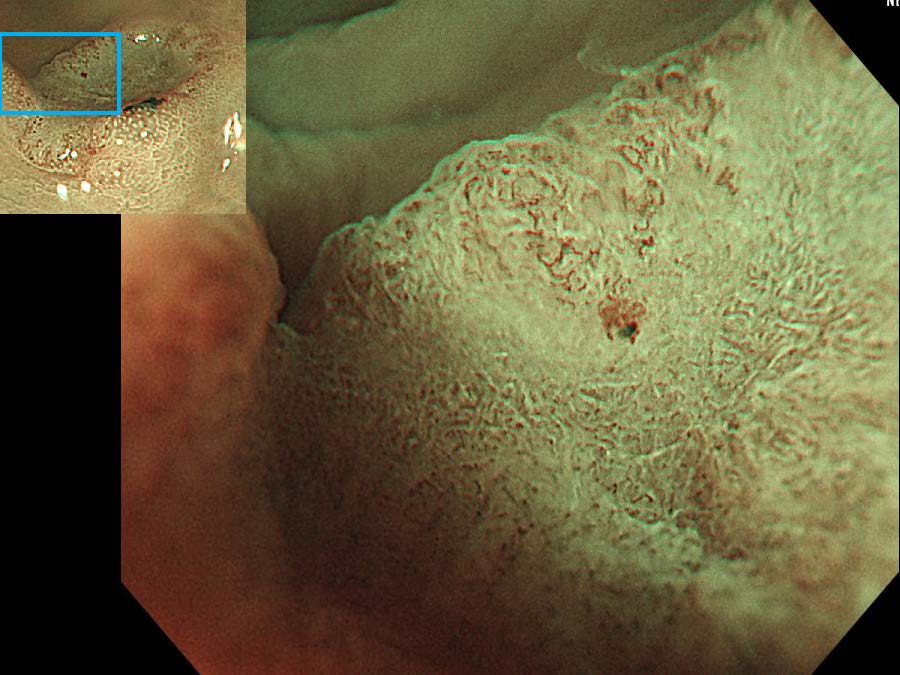

消化管Mapping~大腸~ 2021.10.27

消化器センター 消化器内科

消化管Mapping

消化管Mapping~大腸~

内視鏡検査・治療